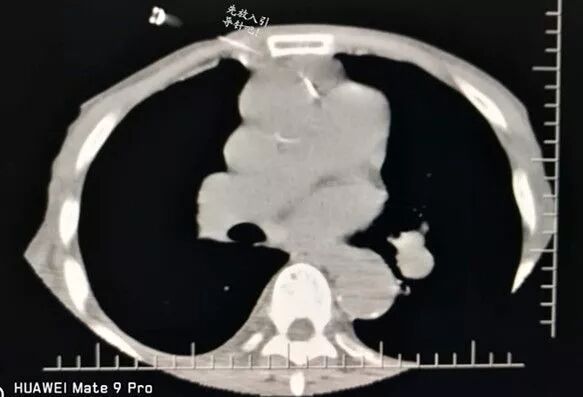

選擇右成角入路,穿越胸骨與主動脈間隙,該間隙僅僅10mm,并避開右胸廓內動脈,精細操作,先置入導針

再置入16G切割活檢槍,稍有偏差便可導致升主動脈損傷破裂,導致災難性后果發(fā)生。

順利規(guī)避大血管進入靶病灶,激發(fā)活檢槍后完成病變組織切割取材。